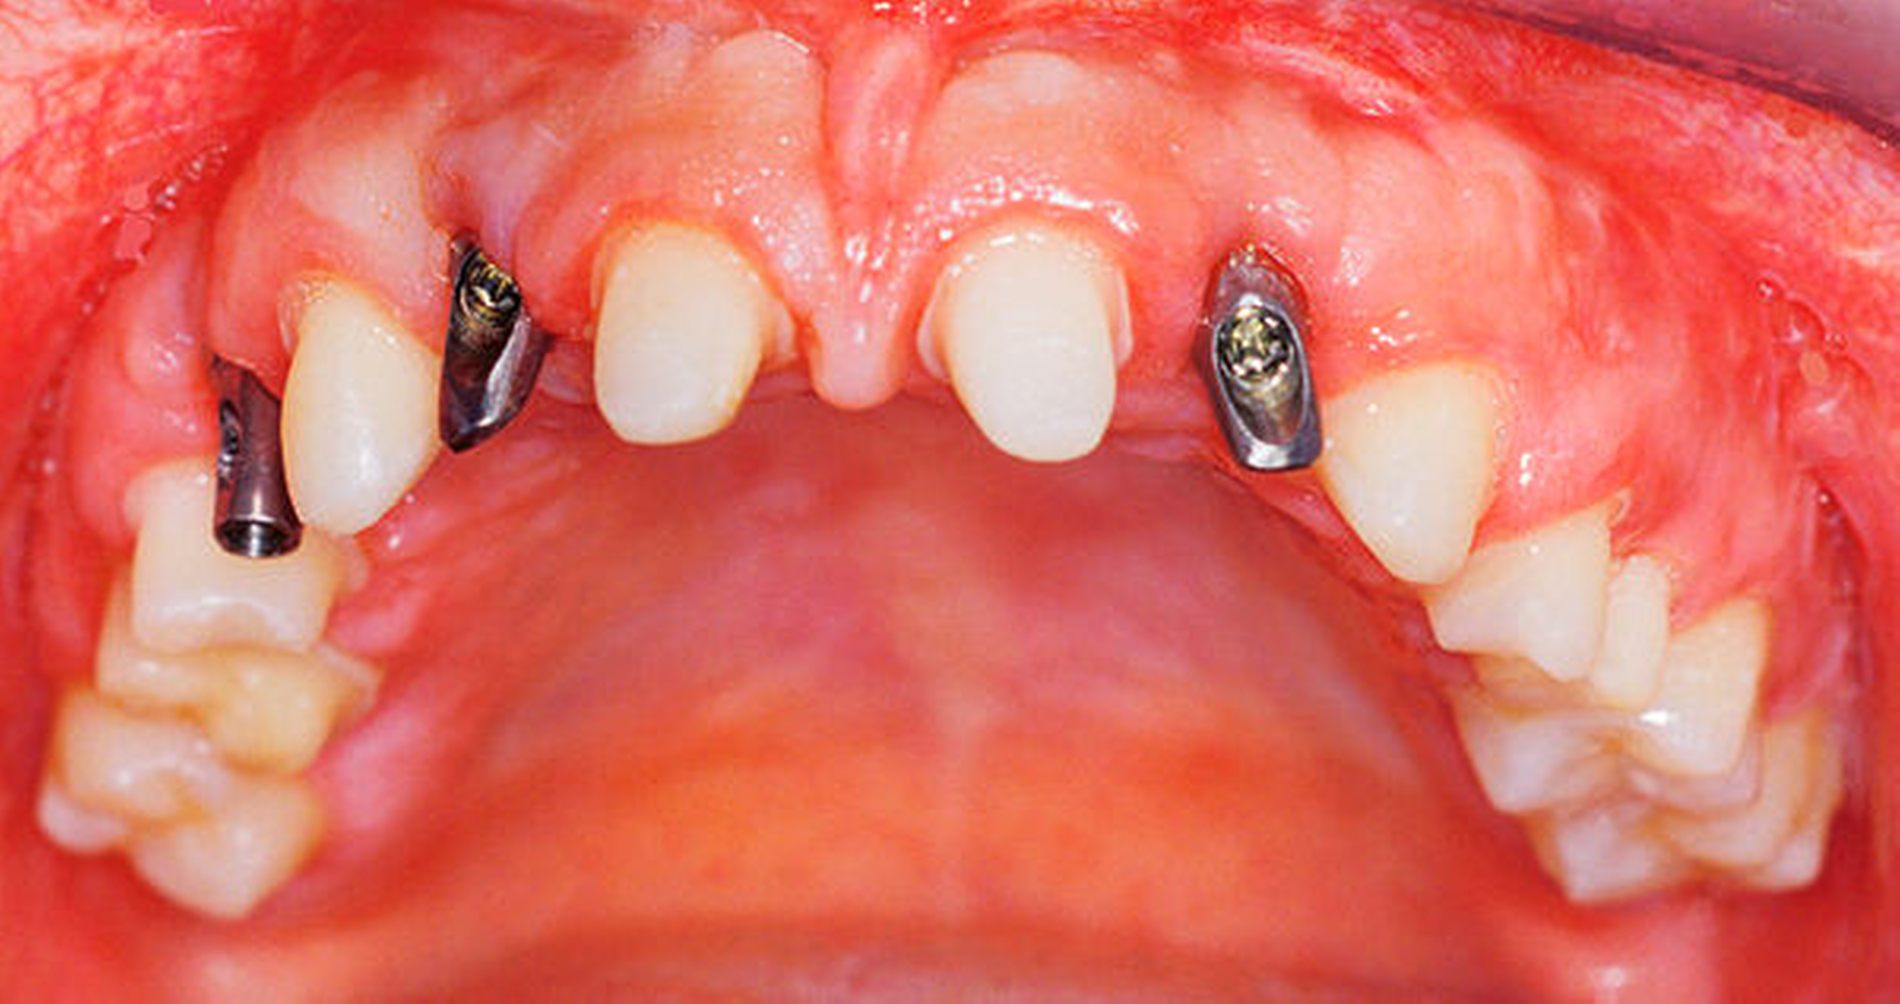

In mehreren Schritten wurden circa vier bis zwölf Monate später in Lokalanästhesie Implantate in den Regionen 12 und 22 (Straumann Narrow Neck) sowie 14, 33 und 44 (Straumann Regular Neck) gesetzt (Abbildung 8a). Zur Verlängerung der kurzen klinischen Kronen 11 und 21 wurde in diesem Bereich die Gingiva im Sinne einer Konturierung elektrotomiert (Abbildung 8b).

Nach viermonatiger Einheilzeit des letzten Implantats erfolgte nach diagnostischem Aufwachsen die Präparation und Abformung des Großteils der Zähne im Ober- und im Unterkiefer zugleich mit der offenen Abformung der Implantate (Abbildung 9). (Zur Erleichterung der Bissnahme wurden vorerst einige Molaren belassen und erst in einer zweiten Etappe beschliffen und versorgt.) Nach Montage der Modelle wurden Lithiumdisilikat-Restaurationen für die natürlichen Zähne und verblendete Zirkonoxidkronen auf konfektionierten, individualisierten Titanabutments (Abbildung 10) hergestellt. Nach einer Einprobe wurden die Kronen auf den Zähnen adhäsiv, die Implantatkronen konventionell mit einem Zinkoxidphosphat-Zement eingesetzt. Die Behandlung der restlichen Zähne wurde in analoger Weise durchgeführt.